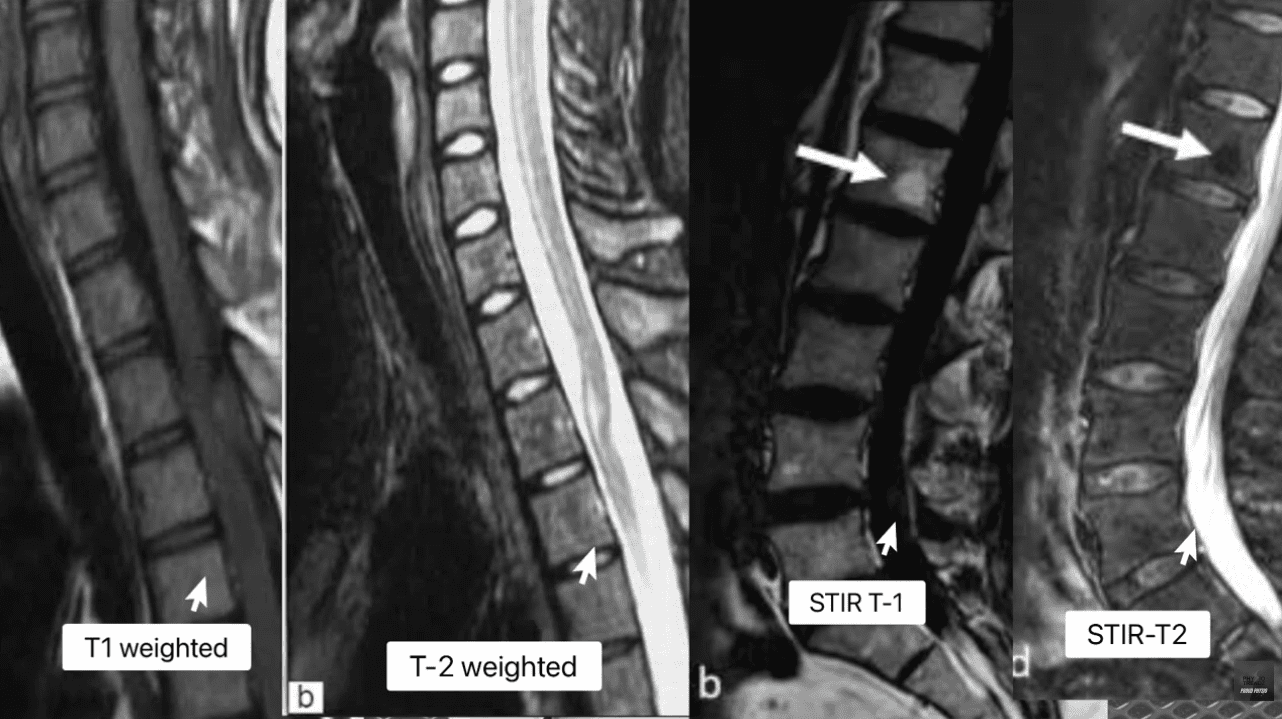

1.2 Decoding the Spinal Pathologies: T1, T2, STIR, and the Critical Role of Edema

Effective MRI interpretation depends on a deep understanding of various pulse sequences and their physiological meanings (Advanced MRI Interpretation of Spinal Pathologies, n.d.). Our team meticulously reviews the T1-weighted, T2-weighted, and Short Tau Inversion Recovery (STIR) sequences to build a precise picture of tissue health, fluid content, and fat presence (Spinal Diagnostics, n.d.).

- T1-Weighted Images: Best for visualizing anatomy and fatty tissue (which appears bright).

- T2-Weighted Images: Best for visualizing fluid (which appears bright), making them excellent for identifying edema and inflammation.

- STIR (Short Tau Inversion Recovery): A crucial sequence that suppresses the fat signal, making it highly sensitive for detecting bone marrow edema and interstitial fluid (inflammation) that is masked by fat on T1 or T2 sequences (Spinal Diagnostics, n.d.).

The presence of edema (abnormal fluid accumulation) in the bone marrow or soft tissues surrounding the spine is a powerful, objective indicator of acute trauma. Edema is the body’s immediate inflammatory response to injury and provides the temporal signature required for injury dating.

- Modic Type 1 (MC1)—The Acute Signature: MC1 represents the acute inflammatory stage characterized by bone marrow edema and vascularized granulation tissue (Wang et al., 2017).

- MRI Appearance: On T1-weighted images, it looks dark (hypointense), and on T2/STIR-weighted images, it looks bright (hyperintense) (Spinal Diagnostics, n.d.).

- Timeline: MC1 changes appear relatively soon after the acute injury and are generally associated with persistent, active inflammation and pain. They typically resolve or transition to Type 2 changes in approximately 6 to 8 weeks (Spinal Diagnostics, n.d.). The presence of Modic Type 1 changes is therefore a strong, objective sign of recent trauma, often correlating with higher pain scores (Jensen et al., 2024).